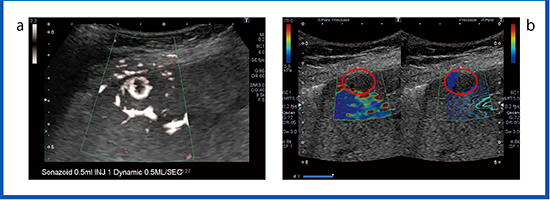

造影SMIが有用であったFNHの症例を示す(図3)。血管相(図3 a)において多血性の腫瘤が認められ,経験豊富な医師は血流が中心から周囲に向かって流れていることを理解できるが,経験の浅い医師には多血性腫瘍と見誤り,FNHと診断することが困難と考えられる。そこで,造影SMI(図3 b)を行うことにより,中心から放射状に広がる血管構築が明瞭に描出され持続的に観察でき,FNHと診断できる。FNHのように多血性で血管構築が明瞭な症例や,HCCにおけるバスケットパターンなどに造影SMIは有用である。

図3 FNHの造影SMI

a:造影超音波 b:造影SMI